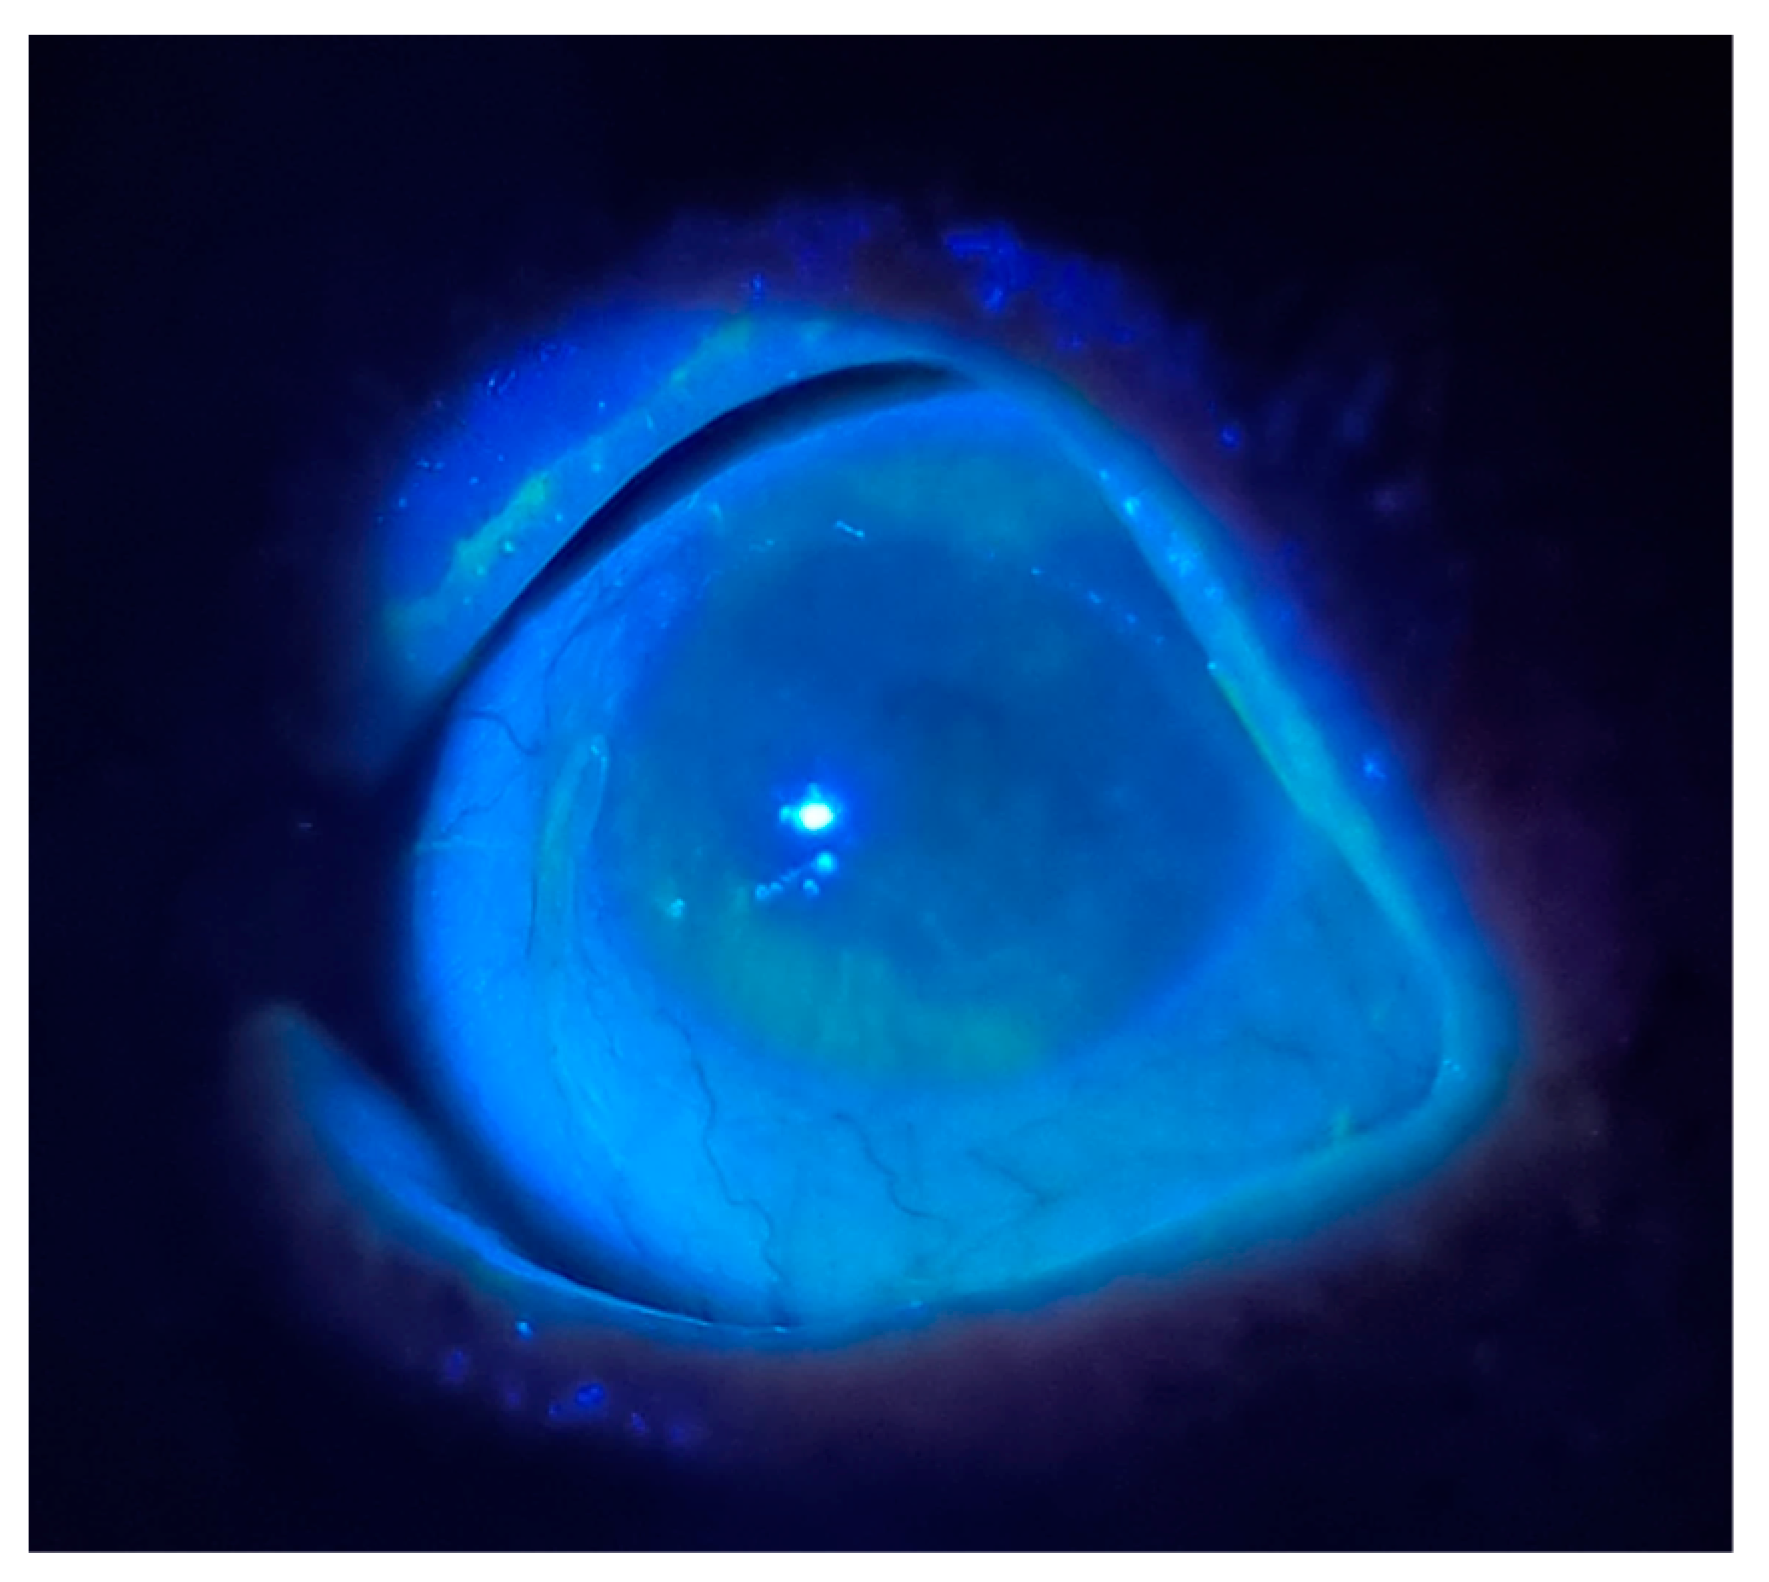

- Fluorescein Dye: Fluorescein sodium may be applied to the corneal surface to visualize abrasions and DED. It can be applied via a drop (2 µL of a 1% solution) or pre-prepared fluorescein-stained strip. When visualized under cobalt-blue light, fluorescein-stained epithelium will shine bright green [59]. PCPs can accomplish this exam using the blue light from the ophthalmoscope (Figure 2). Visualization of the disrupted integrity of the tear film and damage to the corneal epithelium is particularly useful in assessing DED (Figure 2).